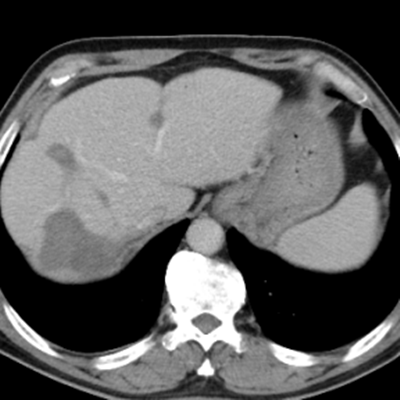

隨后,根據(jù)基因檢測(cè)結(jié)果制定了化療+靶向治療方案。經(jīng)過精準(zhǔn)治療,劉大爺?shù)牟≡畲笮⊙杆倏s小,病灶數(shù)量不斷減少,影像學(xué)評(píng)估已經(jīng)看不見之前那些小的病灶了。

治療后:未見明顯活性轉(zhuǎn)移腫瘤